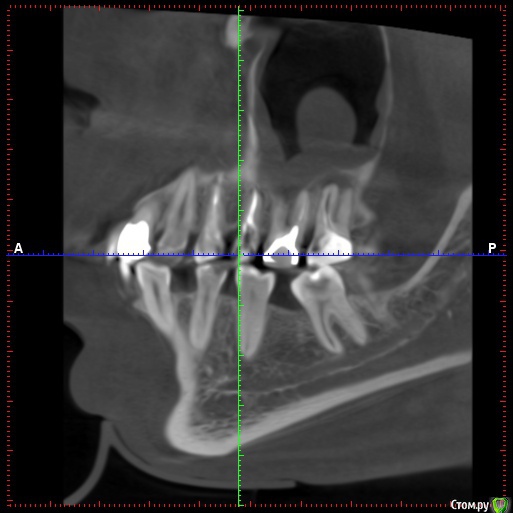

klemento Опубликовано 28 ноября, 2019 Автор Поделиться Опубликовано 28 ноября, 2019 (изменено) Извините. Вот КТ. 26 удален. 27 25 под вопросом. Так же щелкает челюсть справа и слева могу щелкать самостоятельно.https://drive.google.com/open?id=1f2ptFqgFpPtr9B8FsYOVlTv_BBs7ex2j Изменено 28 ноября, 2019 пользователем klemento Ссылка на комментарий